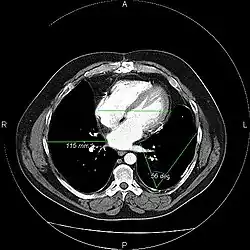

A picture archiving and communication system (PACS) is a medical imaging technology which provides economical storage and convenient access to images from multiple modalities (source machine types).[1] Electronic images and reports are transmitted digitally via PACS; this eliminates the need to manually file, retrieve, or transport film jackets, the folders used to store and protect X-ray film. The universal format for PACS image storage and transfer is DICOM (Digital Imaging and Communications in Medicine). Non-image data, such as scanned documents, may be incorporated using consumer industry standard formats like PDF (Portable Document Format), once encapsulated in DICOM. A PACS consists of four major components: The imaging modalities such as X-ray plain film (PF), computed tomography (CT) and magnetic resonance imaging (MRI), a secured network for the transmission of patient information, workstations for interpreting and reviewing images, and archives for the storage and retrieval of images and reports. Combined with available and emerging web technology, PACS has the ability to deliver timely and efficient access to images, interpretations, and related data. PACS reduces the physical and time barriers associated with traditional film-based image retrieval, distribution, and display.

Most PACS handle images from various medical imaging instruments, including ultrasound (US), magnetic resonance (MR), Nuclear Medicine imaging, positron emission tomography (PET), computed tomography (CT), endoscopy (ES), mammograms (MG), digital radiography (DR), phosphor plate radiography, Visible Light Photography (VL), Histopathology, ophthalmology, etc. Additional types of image formats are always being added. Clinical areas beyond radiology; cardiology, oncology, gastroenterology, and even the laboratory are creating medical images that can be incorporated into PACS. (see DICOM Application areas).

Typically a PACS consists of a multitude of devices. The first step in typical PACS systems is the modality. Modalities are typically computed tomography (CT), ultrasound, nuclear medicine, positron emission tomography (PET), and magnetic resonance imaging (MRI). Depending on the facility's workflow most modalities send to a quality assurance (QA) workstation or sometimes called a PACS gateway. The QA workstation is a checkpoint to make sure patient demographics are correct as well as other important attributes of a study. If the study information is correct the images are passed to the archive for storage. The central storage device (archive) stores images and in some cases reports, measurements and other information that resides with the images. The next step in the PACS workflow is the reading workstations. The reading workstation is where the radiologist reviews the patient's study and formulates their diagnosis. Normally tied to the reading workstation is a reporting package that assists the radiologist with dictating the final report. Reporting software is optional and there are various ways in which doctors prefer to dictate their report. Ancillary to the workflow mentioned, there is normally CD/DVD authoring software used to burn patient studies for distribution to patients or referring physicians. The diagram above shows a typical workflow in most imaging centers and hospitals. Note that this section does not cover integration to a Radiology Information System, Hospital Information System and other such front-end system that relates to the PACS workflow.